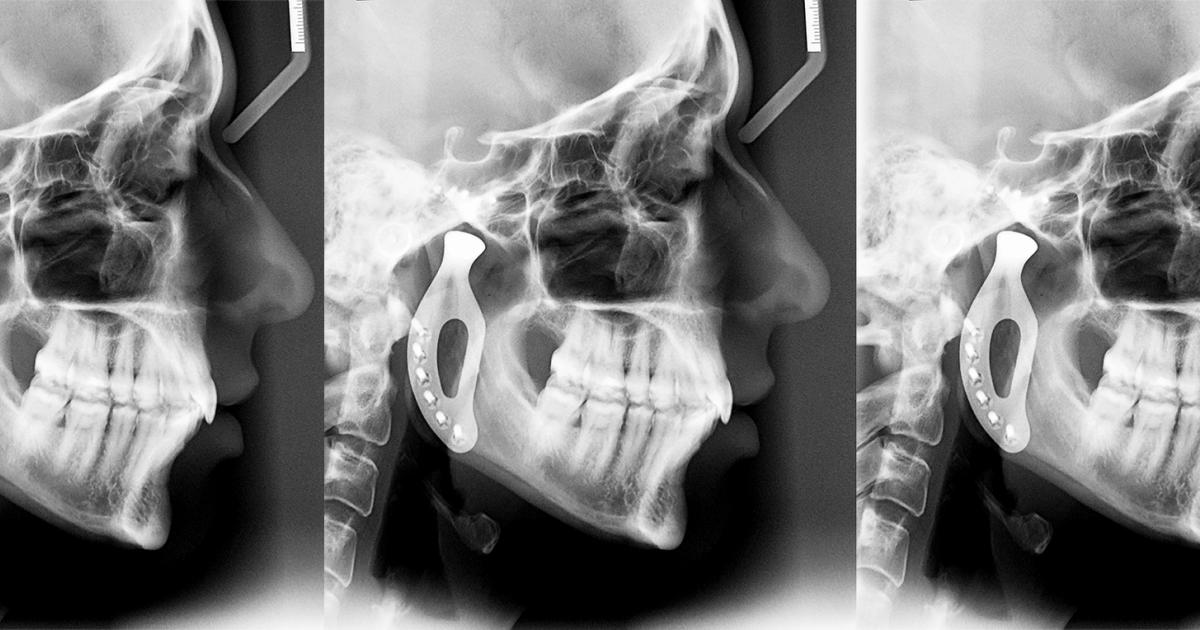

Рентгеновские снимки анкилоза суставов: Как это выглядит